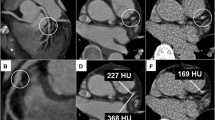

The results of the grey-scale IVUS data are summarised in Table 2. Plaque distribution was found to be concentric in 723 (50.2%) and eccentric in 718 (49.8%) cross-sections. Imaging of landmarks, such as the pericardium, one or more accompanying veins, and side branches, allowed for spatial orientation [9]. Of the 718 eccentric plaques, 401 cross-sections were oriented towards the myocardial side, compared with only 80 that were oriented towards the epicardial side, and 237 that were oriented towards the two lateral quadrants. With regard to the plaque distribution in each individual patient, plaque was more frequently oriented towards the myocardial side (50.2 ± 7.0%) than towards the epicardial (25.6 ± 5.4%) or lateral (14.2 ± 4.4%) side (Fig. 2). Eccentric plaques were more frequently distributed towards the myocardial than towards the epicardial side (p = 0.003). The minimum vessel diameter was significantly smaller at sites where lateral side plaque was observed, compared with sites with epicardial side plaque. The maximum vessel diameter was significantly smaller at sites with lateral side plaque than at sites with myocardial side plaque. The plaque area of lateral side plaques was significantly smaller than that of myocardial or epicardial plaques.

Plaque distribution (%) of the intravascular ultrasound (IVUS) cross-sections in the four quadrants. Of the total plaques, 46.7 ± 7.5% were distributed towards the myocardial side, 20.8 ± 5.0% towards the lateral side, and 12.5 ± 4.2% towards the epicardial side. Data are shown as mean ± SEM. N.S., not significant

We observed TCFAs significantly more frequently in myocardial side plaques (4.99 ± 1.61%) than in lateral side plaques (0.80 ± 0.77%, p = 0.024) or in epicardial side plaques (0%, p = 0.005) (Fig. 3).